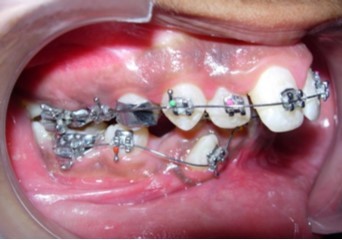

The mandibular first premolars were first extracted to commence treatment of the mandibular arch simultaneously with expansion of the constricted maxilla. Preadjusted edgewise brackets (Roth prescription, 0.022 x 0.028-inch slot) were initially bonded to the maxillary and mandibular teeth. Banded Hyrax (Hygienic rapid palatal expander) was cemented to the maxillary first premolars and molars. (Figure 5). The patient was advised to activate the appliance a quarter turn once or twice a day to achieve adequate expansion consistently. Subsequent to over-expansion of the maxilla the Hyrax was inactivated with a ligature tie tied into the screw holes and was retained in situ for a period of 6 months, after which the maxillary first premolars were extracted and the maxillary arch treatment was commenced.

Figure 5.Rapid palatal expansion appliance in situ

Rapid palatal expansion appliance in situ

Initial alignment was done with upper and lower 0.014-inch nickel titanium archwires (Figure 6a,Figure 6b,Figure 6c). This was followed with 0.016-inch nickel titanium archwires. Space for blocked out 42 was created by an open coil spring on a 0.018-inch stainless steel archwire. Deep bite was corrected with a lower 0.016-inch reverse curve nickel titanium wire. Extraction spaces in the maxillary and mandibular dental arches were closed with 9mm nickel titanium retraction coil springs attached to crimpable hooks on 0.017 x 0.025-inch stainless steel archwires and finishing and detailing was completed with 0.019 x 0.025-inch stainless steel archwires.